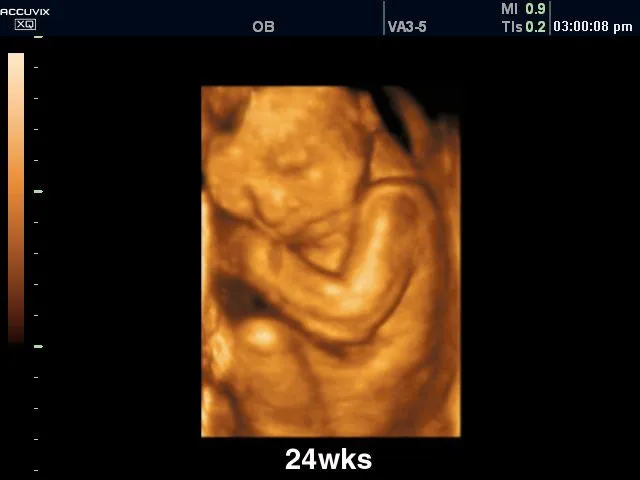

The other image was a miniature doll. $10-25 depending on clay or resin, plastic bulk about $0.50 a piece.

An infant born/miscarriage at 27 weeks looks more like this, with bones the consistency of a gummy bear, and skin almost as thin as tissue paper.

If you use photos, you should know if they are true to life or propaganda.

No way a 12 or 20 weeks looks so well developed and perfect.

images